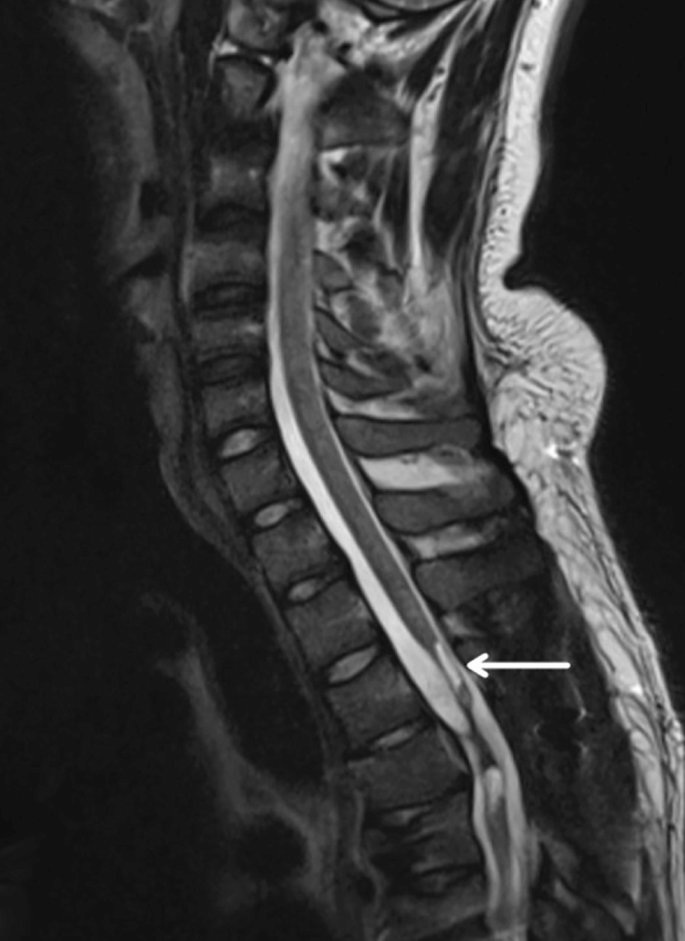

慢性期開(kāi)始于損傷后約3-6個(gè)月,并持續(xù)患者的余生,典型特征是囊腫形成和嚴(yán)重的神經(jīng)膠質(zhì)瘢痕(圖2)。

圖2:X射線(xiàn)圖像顯示慢性期脊髓損傷,通常以囊腫形成為特征,如白色箭頭所示